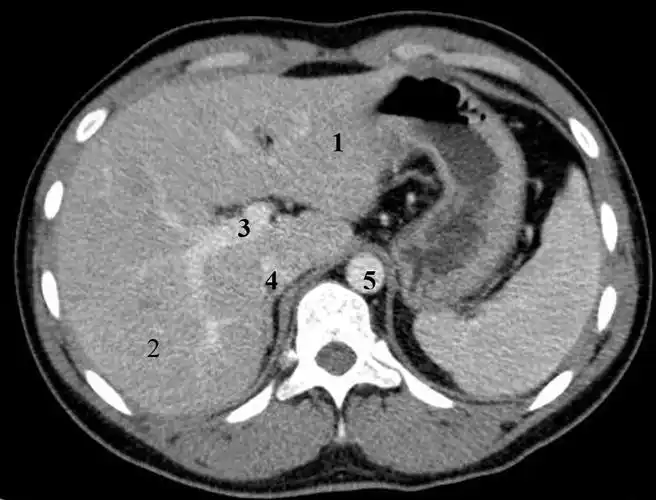

肝外伤影像学之:计算机断层扫描(ct)

肝癌破裂出血ct表现

结合解剖看腹部ct,轻松掌握肝脏读片!_静脉_水平_脏器